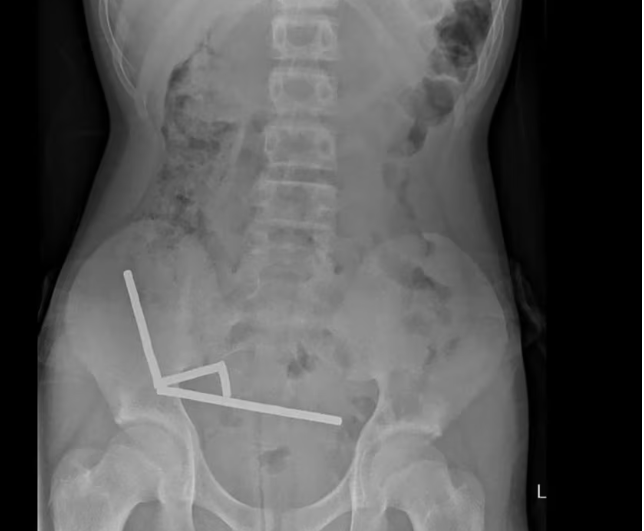

Skanimet treguan se magnetët ishin grumbulluar në anën e djathtë të poshtme të barkut, duke tërhequr pjesë të ndryshme të zorrës me forcën e tyre magnetike. Disa imazhe mjekësore ishin shtrembëruar për shkak të magnetëve.

Mjekët kryen një ndërhyrje kirurgjikale eksploruese dhe zbuluan se magnetët kishin shkaktuar nekrozë nga presioni në disa pjesë të zorrës dhe të zorrës së trashë. Ata arritën t’i hiqnin magnetët me sukses, por djali humbi një pjesë të zorrës. Ai qëndroi tetë ditë në spital për rikuperim para se të dilte.